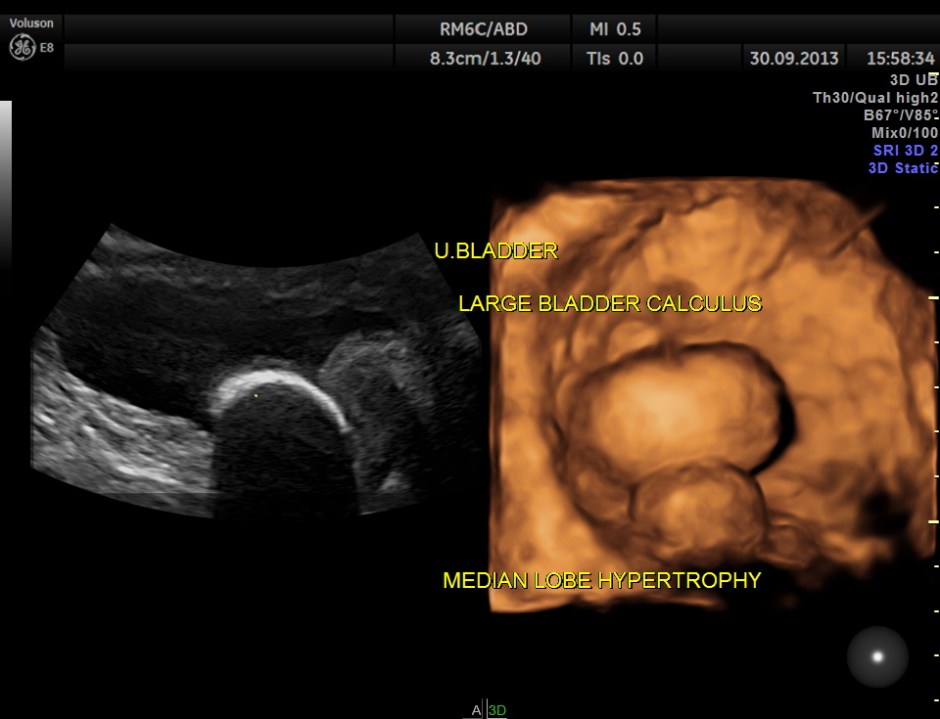

urinary bladder showed a large calculus and prominent swelling of the median lobe of the prostate.

2 D and 3 D of the bladder calculus alone.

2 D and 3 D views of the median lobe hypertrophy

The diagnosis given was Large calculus in the urinary bladder , Severe prostatic enlargement with prominent median lobe hypertrophy , causing Right sided obstructive uropathy.

The diagnosis was made with the 2D images , but the 3 D images were very helpful in explaining to the patient.